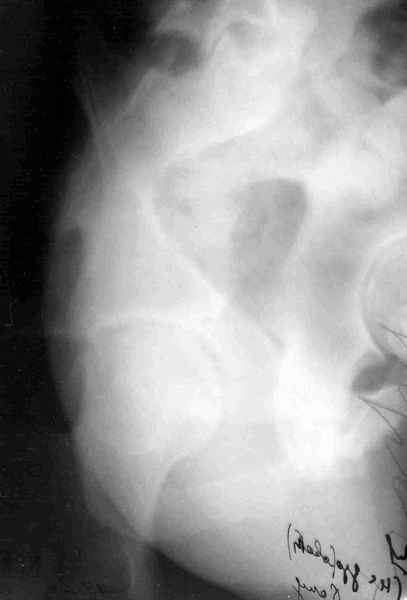

11Judet 1Judet 2

Согласно договорённости с А.В. Рунковым высылаю КТ и скиаграмму (со сканами рентгенограмм опять проблемы) 29-летнего пациента после автотравмы. С Уважением Андрей Стасюк